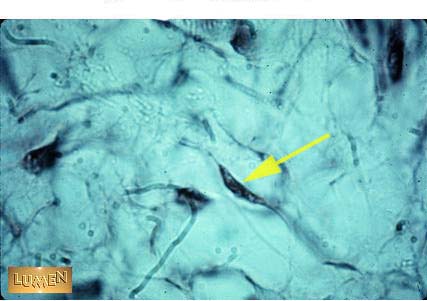

What cell is identified by the pointer?

fibroblast